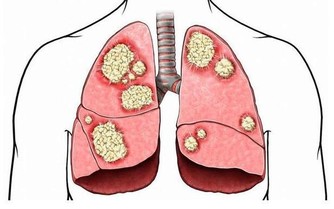

溫熱毒邪開始活動,現代醫學所說的流感、流腦、麻疹、猩紅熱、肺炎也多有發生和流行。

此外,注意口鼻保健,阻斷溫邪上受首先犯肺之路。